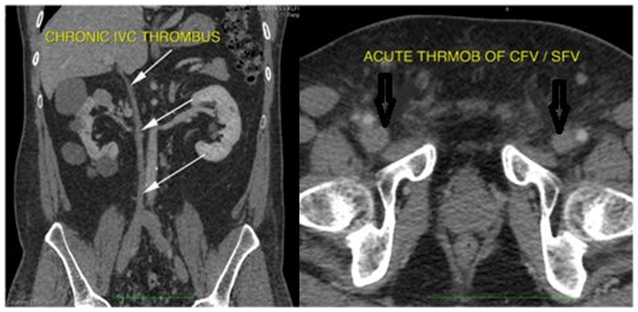

2-D ECHO showed good biventricular function, EF-62%, type 1 diastolic dysfunction, myxomatous AML suggestive of mitral valve prolapse(MVP) (Figure 4).

Figure 4 2-D ECHO showing myxomatous AML (arrow) suggestive of mitral valve prolapse(MVP).

ADPKD is associated with MVP in up to 25%.4 There are rare case reports of thrombosis in the inferior vena cava (IVC) due to enlarged cysts in autosomal dominant polycystic kidney disease.5 Our patient showed number of cysts to meet the required criteria for ADPKD6, with Stage II CKD, MVP, multiple colonic diverticulae and IVC thrombosis, had no positive family history, with only elder brother having late onset minimal change disease. Genetic workup for ADPKD is done. Literature review did not show association of IVC hypoplasia with cystic kidney disease.